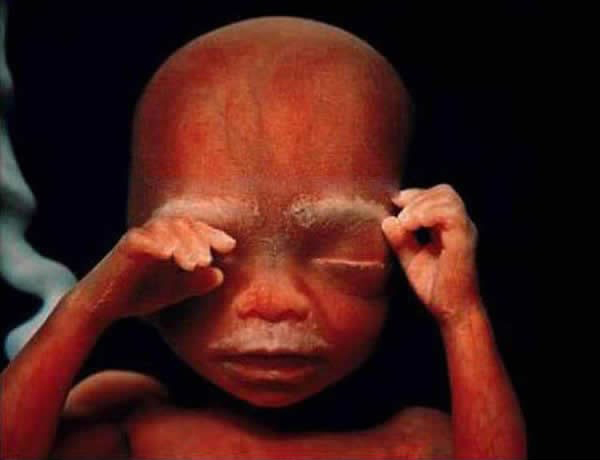

18. hét

20. hét, kialakul a babát védő szőrzet